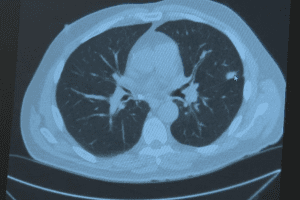

Istanbul's treatment costs for demyelinating diseases typically run 40–60% lower than Valencia's private sector prices. When including accommodation and daily expenses, the total trip cost often favors medical tourism for Spanish patients. Valencia typically range from €150–€300 per visit, with advanced MRI imaging (€800–€1,500), cerebrospinal fluid analysis (€200–€400), and specialized immunotherapy treatments varying widely based on the specific demyelinating disease diagnosis and treatment protocol chosen. Istanbul, Turkey's largest metropolitan centre, hosts multiple JCI-accredited hospitals with specialized neurology departments offering comparable diagnostic and treatment services at approximately 40–60% lower cost. Beyond the treatment itself, the total trip cost comparison reveals additional savings: accommodation in Istanbul costs substantially less than Valencia, daily living expenses are lower, and many Turkish hospitals provide coordinated transfer and lodging packages that simplify budgeting. For a Spanish patient evaluating whether to pursue treatment locally in Valencia or travel to Istanbul, the financial analysis often tips significantly toward medical tourism when considering not just the procedure cost but the entire healthcare journey from initial consultation through recovery and follow-up care.

Turkish neurology centres offer multidisciplinary treatment combining advanced diagnostics, disease-modifying therapies, and specialized monitoring. Treatment plans are individualized based on disease type and patient-specific clinical factors. nd disease-modifying immunotherapies tailored to specific diagnoses such as multiple sclerosis, neuromyelitis optica spectrum disorder, or transverse myelitis. Treatment planning emphasizes multidisciplinary collaboration among neurologists, neuroimmunologists, rehabilitation specialists, and nursing staff to create individualized protocols based on disease type, severity, and patient-specific factors. Many Turkish hospitals offer both conventional immunosuppressive therapies and newer biologic agents, with specialist teams experienced in managing relapse episodes and providing long-term disease management strategies. The centres maintain modern diagnostic laboratories capable of conducting complex immunological testing, neurophysiological studies, and brain/spinal imaging to support accurate diagnosis and treatment monitoring. This comprehensive, individualized approach—combined with ongoing follow-up care coordination—ensures that each patient receives treatment options matched to their unique clinical presentation rather than a one-size-fits-all protocol, distinguishing Turkish providers as serious specialists in complex neurological conditions.